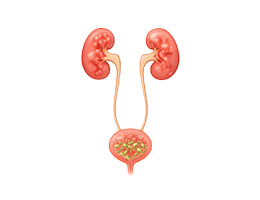

요로감염 (Urinary Tract Infection (UTI))